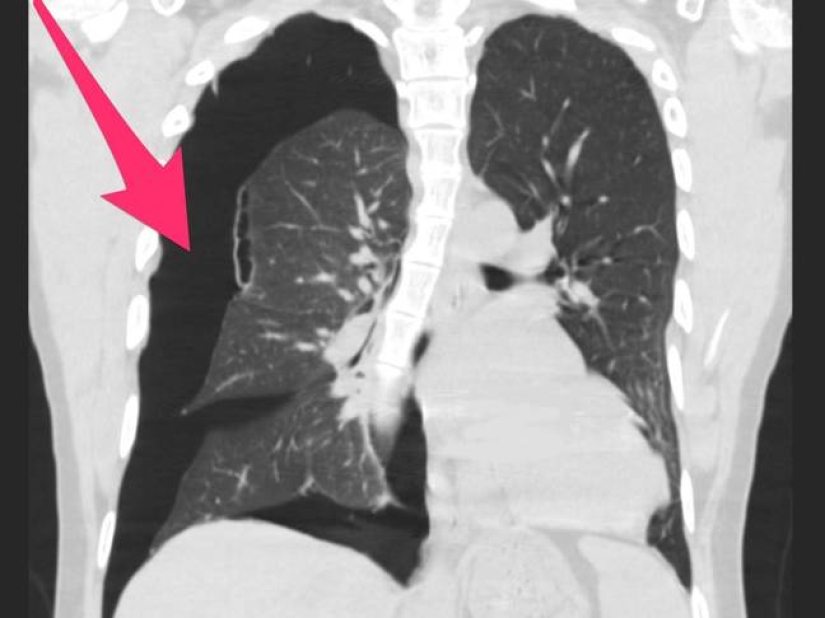

Doctors decided to publish X-rays of smokers' lungs after a series of deaths associated with the use of vaping to warn everyone about its harm.

A fashionable hobby brings young people to the grave, who are happy to inhale fragrant smoke. Harmless, at first glance, infatuation leads to irreversible consequences. X-rays of the lungs of vape smokers are irrefutable proof of the harm of electronic hookahs. We hope this information will pop up in your head before the next puff.